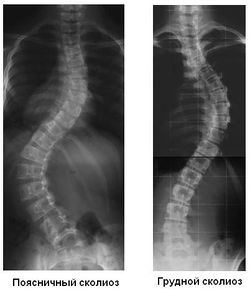

Сколиоз (греч. σκολιός — «кривой», лат. scoliōsis) - это нарушение осанки в следствии искривления позвоночника во фронтальной плоскости (вправо или влево) различного генеза.[1] В отличие от искривлений в сагиттальной плоскости (кифоза, лордоза) всегда является патологическим. При массовых обследованиях та или иная степень сколиоза обнаруживается у 10-28 % населения. Чаще всего это небольшая степень искривления, до 20 градусов.[2]

В тяжелых случаях искривление появляется и в других плоскостях: в сагитальной (вперед или назад) и в аксиальной (торсия или скручивание позвонков и их частей).[3]

Рентгенологическая классификация (по В. Д. Чаклину):

- 1 степень сколиоза. Угол сколиоза 1° — 10°.

- 2 степень сколиоза. Угол сколиоза 11° — 25°.

- 3 степень сколиоза. Угол сколиоза 26° — 50°.

- 4 степень сколиоза. Угол сколиоза > 50°.;